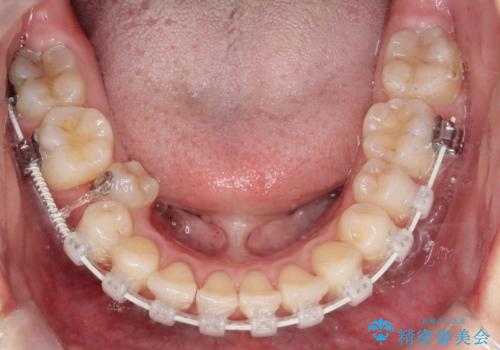

右下第二小臼歯の舌側転移の改善

- 患者様は、右下第二小臼歯が舌側に転移していることが主訴でした。診断の結果、抜歯を伴う矯正治療も検討しましたが、奥歯の遠心移動とIPR(インタープロキシマルリダクション)を行うことで、非抜歯で矯正を進めることが可能であると判断しました。治療計画では、審美ワイヤーを用いた2年間の治療で、歯列を整えつつ、臼歯関係や正中のバランスを維持しながら進めました。